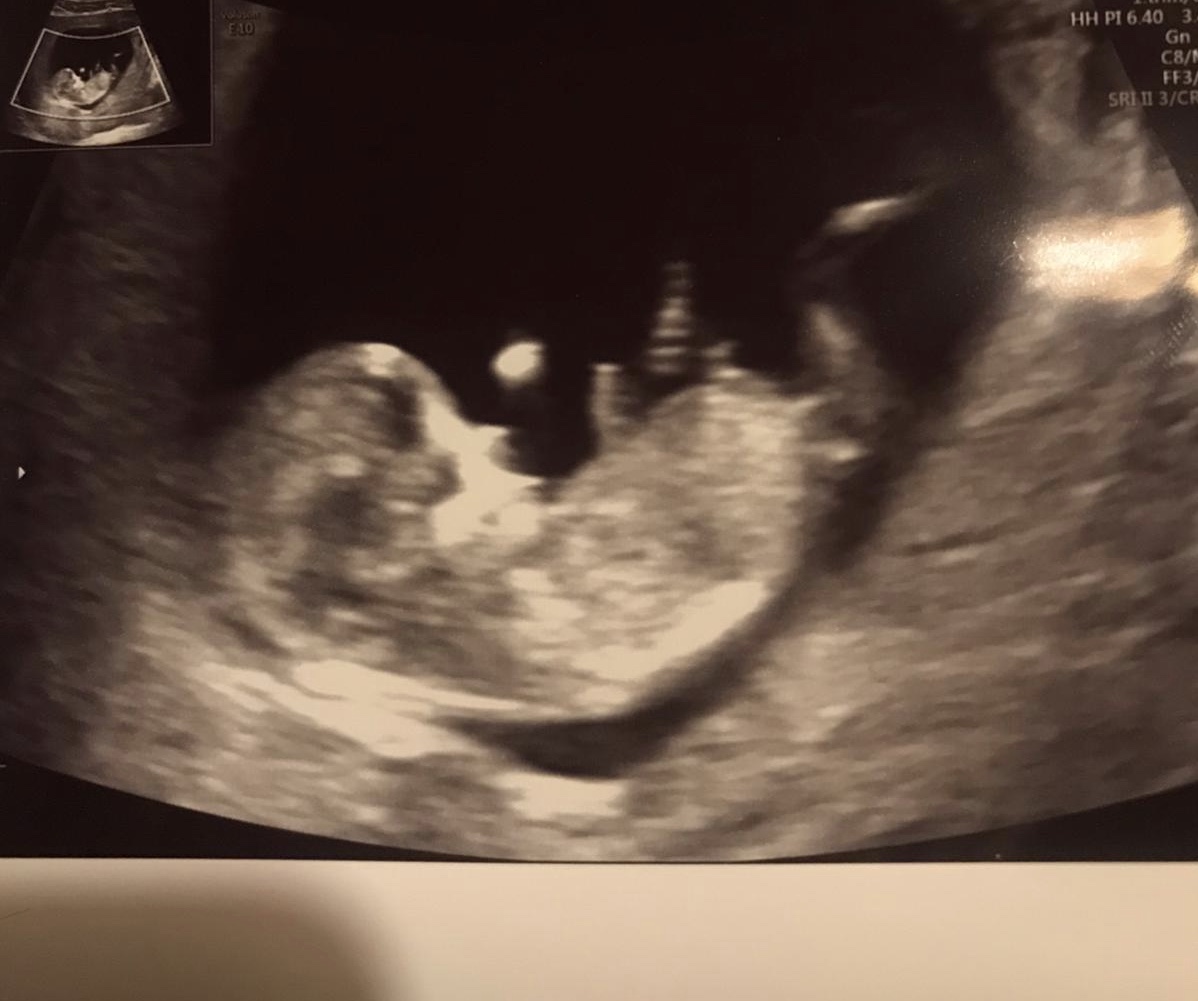

Rekli byste, ze jde z teto fotecky poznat pohlavi ? 😊

Holčička nebo kluk. Poznáte?